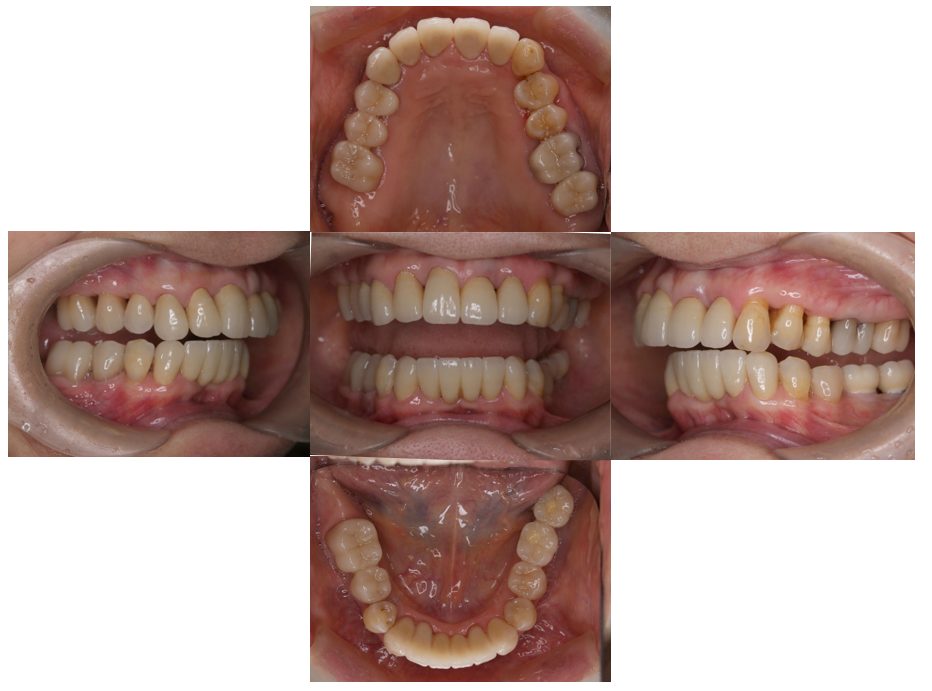

矯正治療・インプラント治療・セラミック治療の症例紹介(三隅歯科クリニック)

三隅 賢祐(三隅歯科クリニック)

症例詳細

| 主訴 | 30代女性 顎関節が痛い。見た目も気になる |

| 治療内容 | 矯正治療を行いました。 |

| 治療費 | 1,700,000円(税込み) |

| 治療期間 | 3年(矯正治療期間 2年半) |

| 治療回数 | 40回 |

| 想定されたリスク | 術前に精密な診査診断とシミュレーションを行い、インプラントを適正なポジションに埋入しておかないと、インプラント自体が矯正治療の邪魔になるリスクがあった。 |